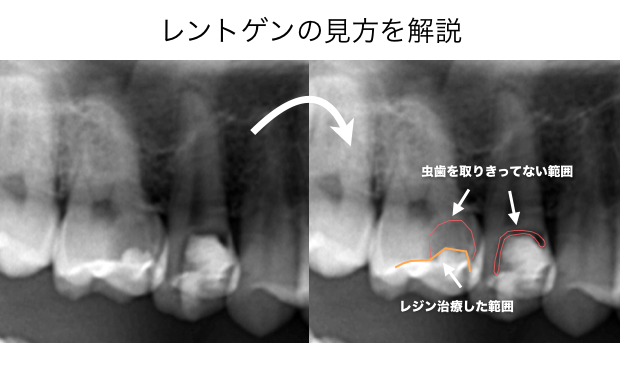

CASE1

CASE2

CASE3

CASE4

以前治療した銀歯の内部から虫歯の取り残しが見つかった症例

CASE5

CASE6

CASE7

CASE8

最近治療した歯の内部から虫歯が見つかった症例

レントゲンで見ると虫歯の範囲は、透過像として判断できます

透過像とはレントゲンで黒くなっている部分です

空洞になるとレントゲンでは黒く写ります

歯を直接見て綺麗なのに内部に透過像があると虫歯の取り残しの可能性があります

CASE9

以前治療したレジン治療の内部から虫歯の取り残しが見つかった症例

CASE9

銀歯の内部で虫歯の取り残しがあった症例

CASE10

レジン治療の内部で虫歯の取り残しがあった症例

CASE11

1本の歯に2回連続で虫歯の取り残しが見つかった症例